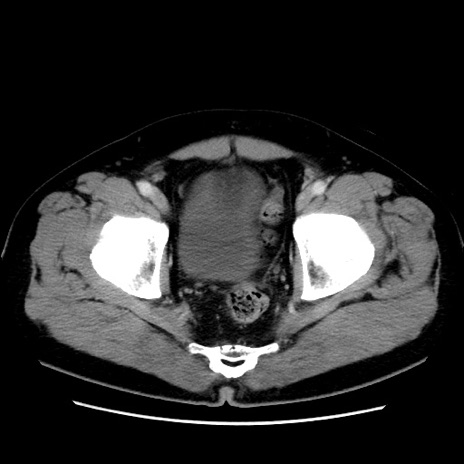

症例16(横断像)

【症例】 70歳代男性

【主訴】 腹痛、嘔吐

【現病歴】 約1ヶ月前より間欠的に腹痛と嘔吐あり、当院消化器内科を受診したところCTで多発する肝臓のLDAを指摘され、精査中であった。以降は消化器症状は安定していたが、2日前より嘔気と腹痛があり、同日より排便・排ガスが消失した。改善認めず、 本日、救急外来を受診した。

【既往歴】 大腸ポリープ切除後。

【身体所見】意識清明・会話良好、BT 36.3℃、BP 127/80mmHg、 P 80bpm、腹部:膨満あり、平坦・軟、上腹部正中および下腹部正中に圧痛あり、反跳痛なし、筋性防御なし。

【データ】WBC 7200、CRP 0.77